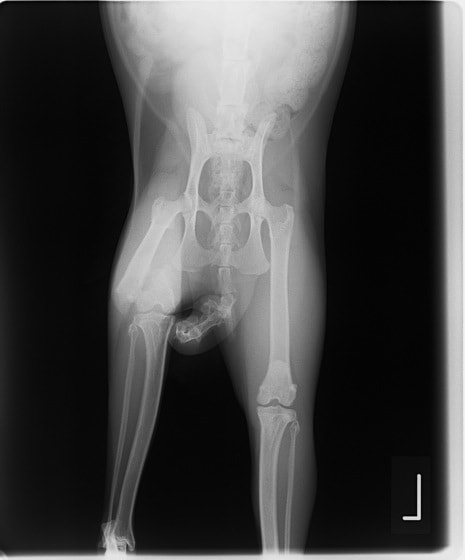

症例3:キルシュナーワイヤーのピンニングによる整復

ペルシャ猫 11ヶ月齢 雄

他院にて左大腿骨遠位の成長板骨折(salter-harrisⅠ型)が認められており、治療相談を目的として来院。当院にて、キルシュナーワイヤーを用いたピンニングにより骨折部位の整復を行いました。術後の経過は良好で、現在も経過観察中です。

術前レントゲン

術後レントゲン